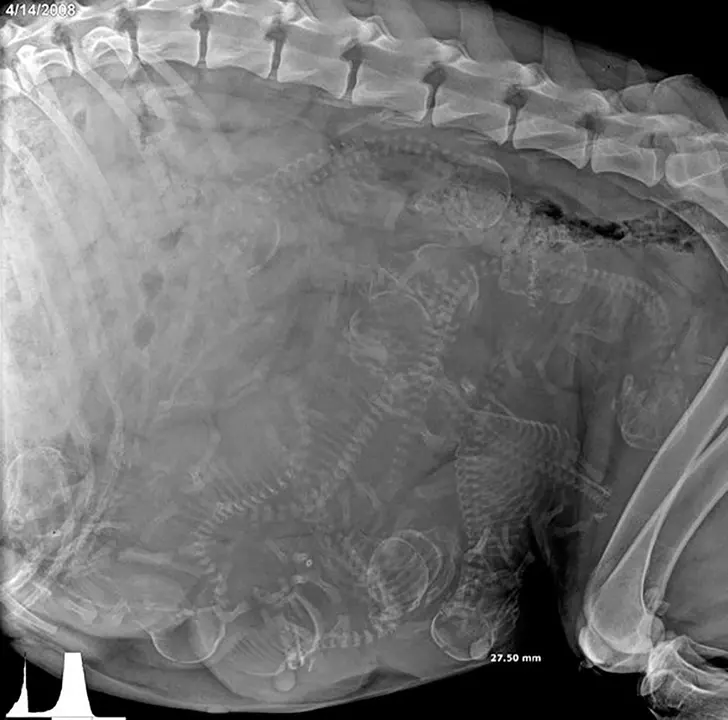

1. นี่เป็นภาพเอกซเรย์ของสุนัขที่กำลงตั้งท้อง

ไหนจะเป็นซากปรักหักพังตั้งแต่ยุคกลางใต้โรงยิมของโรงเรียน หรือว่าจะเป็นภาพเอกซเรย์ของสุนัขที่ท้องอยู่ พวกนี้เป็นแค่น้ำจิ้มของสิ่งมหัศจรรย์มากมายของโลกเราใบนี้